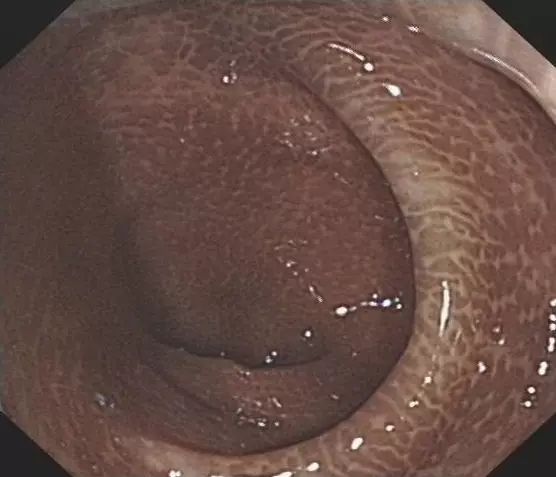

大肠黑变病是一种以大肠黏膜色素沉着为特征的非炎症性肠病,肠镜检查可见大肠黏膜有不同程度的色素沉着,轻者有斑点如豹纹样,重者肠腔全部为黑褐色,血管纹理不清楚。